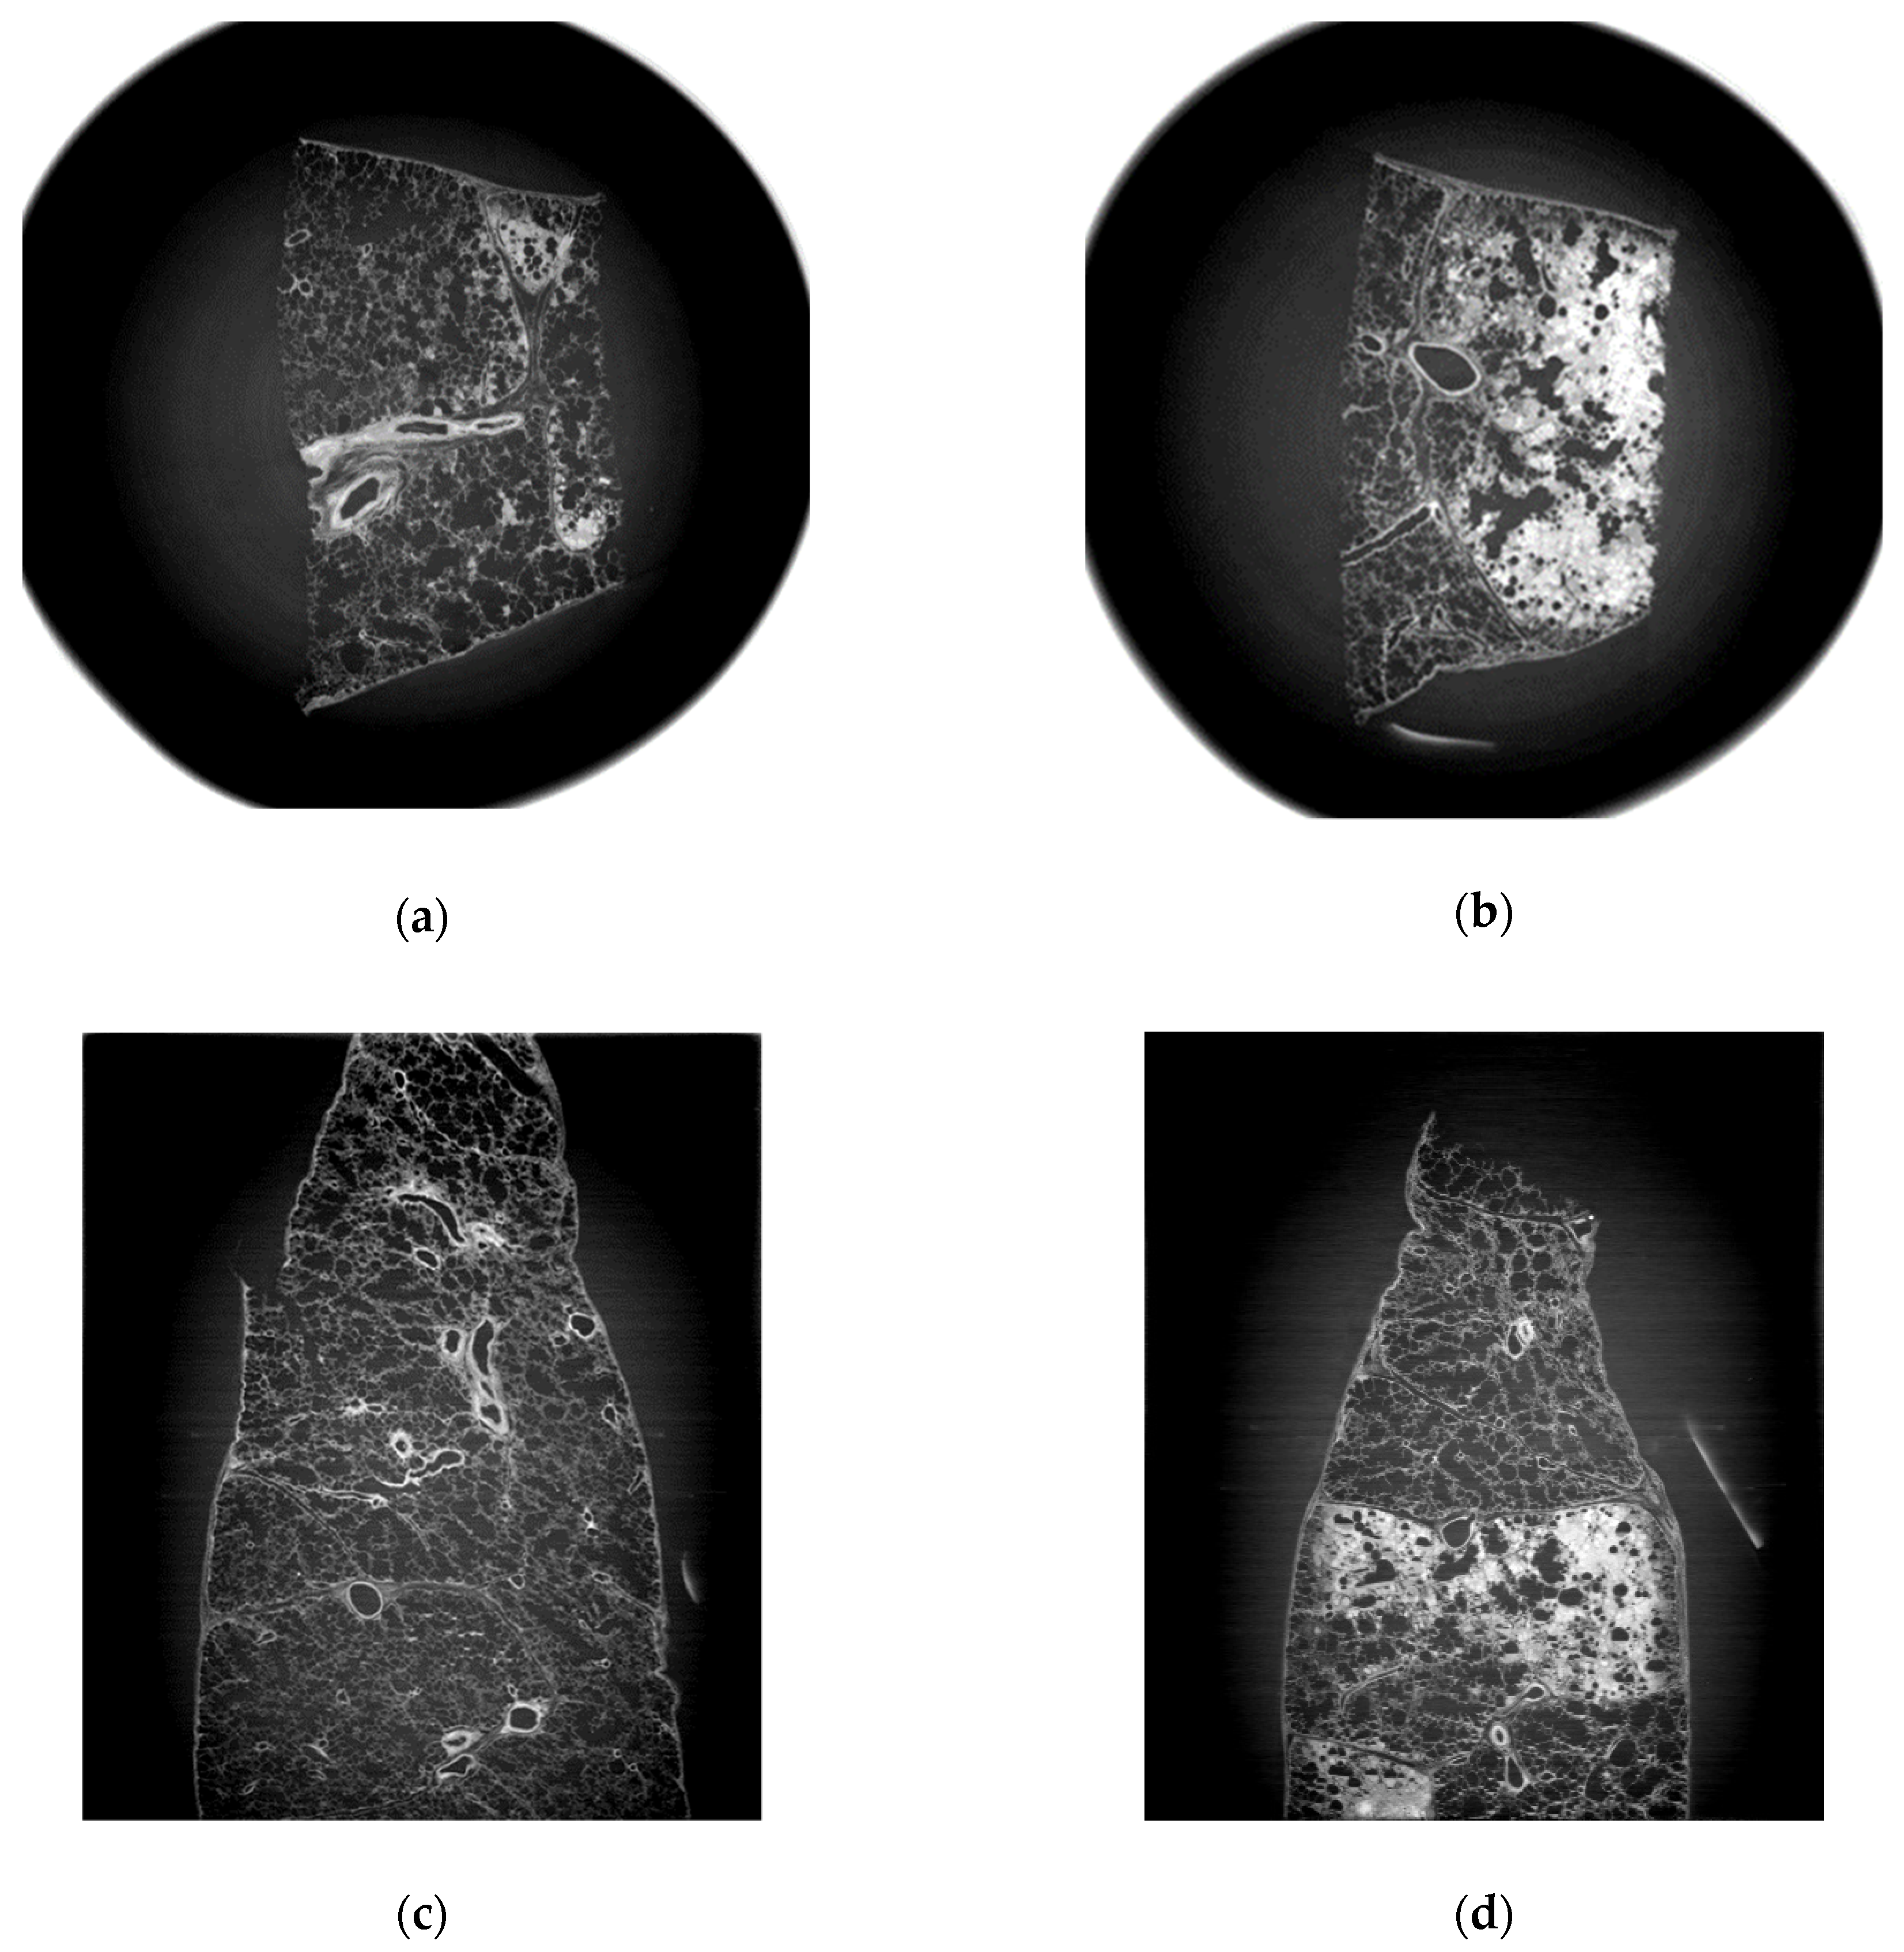

3.1. Refraction-Contrast Synchrotron Tomographic Images of Lung Tissue Including Cancer and 3D Reconstruction

3.2. Comparison with Pathologic Examination